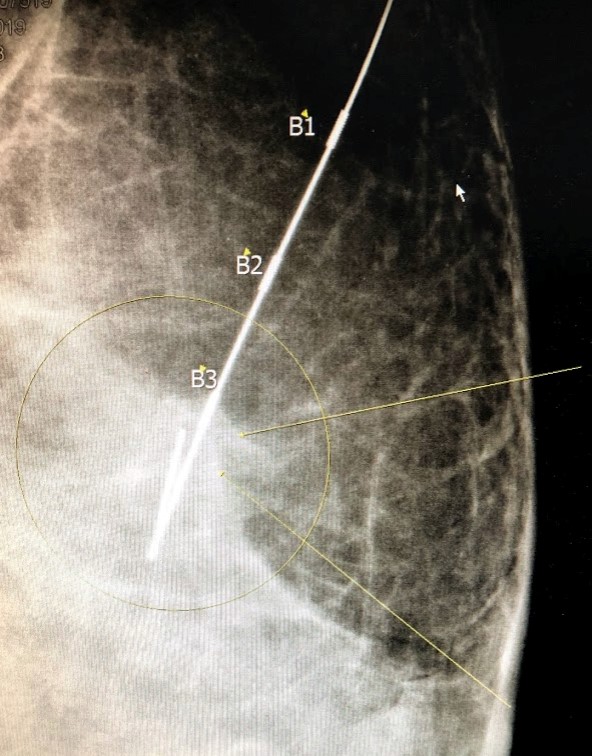

Pelokalan kawat stereotaktik dan biopsi eksisi

Jika area atau pola mikrokalsifikasi lebih luas atau lokasi lebih menantang untuk biopsi inti, maka kawat kait dimasukkan di bawah mamografi untuk membantu melokalisasi jaringan. Setelah kawat kail dipasang di dalam kalsifikasi, pasien dikirim ke ruang operasi untuk biopsi eksisi bedah lesi payudara.

Kawat kait dalam posisi menunjukkan kalsifikasi yang berdekatan dengan penanda B1

Radiografi spesimen setelah jaringan payudara diangkat dengan kawat kait di tempat menunjukkan kalsifikasi termasuk di dalam